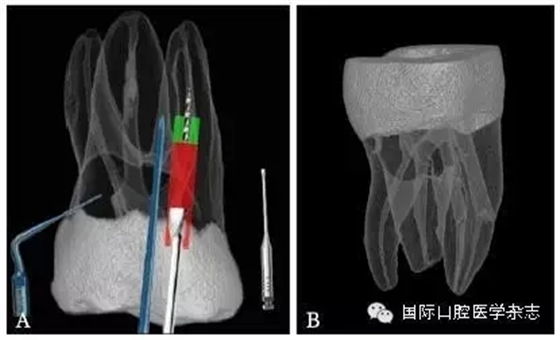

3.2.1 牙本質(zhì)厚度評(píng)估 取出分離器械需要損失部分牙本質(zhì),牙本質(zhì)的損失量包括縱向損失和橫向損失。縱向損失決定于取出時(shí)分離器械冠方末端需要暴露的長(zhǎng)度,橫向損失決定于分離器械的斷端直徑以及選用取出器械的方法(如超聲法或是環(huán)鉆法等)。牙本質(zhì)損失量過(guò)多會(huì)導(dǎo)致根管穿孔、根管折斷等并發(fā)癥[7](圖3)。

A:紅色及綠色的部分分別表示用改良GG鉆及超聲工作尖去除牙本質(zhì)的量;B:MicroCT掃描圖像顯示取出下頜第一磨牙近頰根管中分離器械后,導(dǎo)致了根管穿孔。

圖 3 取分離器械過(guò)程中會(huì)導(dǎo)致牙本質(zhì)損失,甚至穿孔等并發(fā)癥

取出分離器械后,根管壁的殘余牙本質(zhì)厚度是影響牙根抵抗力的重要因素,因而,可以認(rèn)為殘余牙本質(zhì)的厚度是影響分離器械取出與否的最重要的因素之一[8]。

目前,對(duì)于分離器械周?chē)辣举|(zhì)厚度的評(píng)估以及取出后殘余牙本質(zhì)厚度的預(yù)測(cè)主要需借助影像學(xué)檢查,例如根尖片、錐形束CT(cone beamcomputed tomography,CBCT)圖像等。傳統(tǒng)的平行投照的根尖片無(wú)法反映三維立體結(jié)構(gòu),且往往存在解剖結(jié)構(gòu)影像的重疊,不利于臨床判斷,具有一定的局限性。多位學(xué)者[10]的研究表明:平行投照的根尖片會(huì)高估實(shí)際的牙本質(zhì)壁的厚度。一些學(xué)者[11-12]的研究表明:當(dāng)分離器械位于上頜第一磨牙近中根管時(shí),采用成角投照(21°)的拍攝技術(shù)與平行投照技術(shù)得到的X線(xiàn)片相比,能更準(zhǔn)確地評(píng)估牙本質(zhì)的厚度,為分離器械取出與否提供指導(dǎo)(圖4)。近年來(lái),CBCT在牙髓病學(xué)中的應(yīng)用越來(lái)越廣泛,由于CBCT能清楚地反映牙及牙根周?chē)M織的三維立體結(jié)構(gòu),為牙本質(zhì)厚度的評(píng)估與預(yù)測(cè)提供了可行性(圖5);因此,CBCT在器械分離的病例術(shù)前風(fēng)險(xiǎn)評(píng)估方面具有較好的應(yīng)用前景。

圖 5 使用CBCT評(píng)估分離器械周?chē)辣举|(zhì)厚度